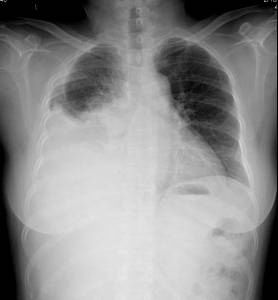

照片名称:左侧胸腔积液